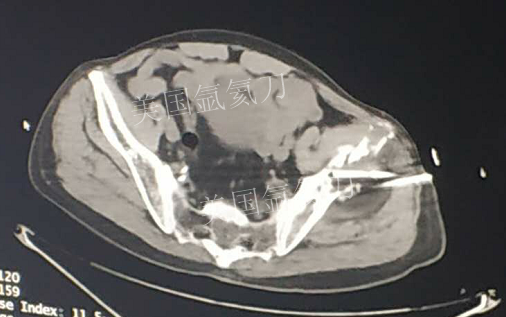

73岁臀部氩氦刀冷冻消融